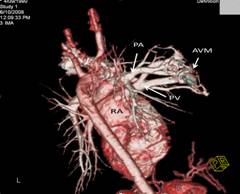

Complete blood count revealed polycythaemia (Hb of 210 g/L; HCT 0.64 L/L). Computed Tomography (CT) brain showed evidence of a right pontine infarct with no suggestion of cerebral arteriovenous malformation. Chest radiograph showed a faint right mid-zone opacity. Transthoracic echocardiography showed no evidence of septal wall defects or large vessel anomalies and no pulmonary hypertension. Plain CT of the chest suggested the presence of a PAVM (Figure 1). This was confirmed by CT pulmonary angiogram which revealed a solitary PAVM with two feeder vessels in the lower lobe of the right lung (Figure 2 and 3).

Figure 2: 2-D reconstruction of CT pulmonary angiogram in early arterial phase reveals the presence of a solitary right PAVM. PA: pulmonary artery; SPV: superior pulmonary vein; AVM: arteriovenous malformation; RA: right atrium.